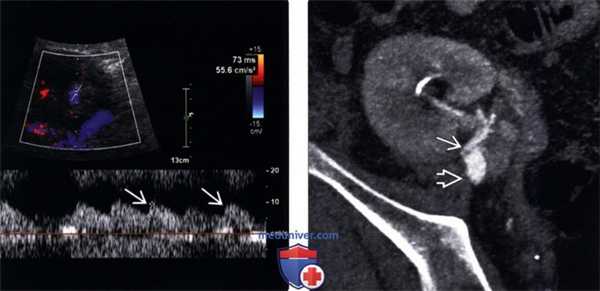

(Левый) При допплерографии сегментарной артерии нижнего полюса трансплантата почки со стенозом почечной артерии визуализируется медленная малая волна со сниженным индексом ускорения =55,6 см/с 2 .

(Правый) КТ артериография, выполненная после выявления медленной малой волны при допплерографии трансплантата от живого неродственного донора. Имеется перекрутв проксимальном отделе почечной артерии. Подвздошная артерия не изменена. При операции произошел избыточный поворот почки.